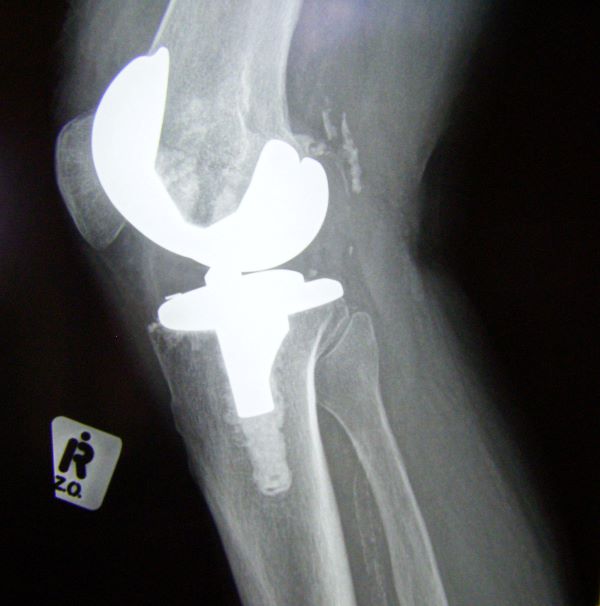

무릎 관절의 퇴행성 변화는 보행 기능에 큰 지장을 초래하며, 통증과 기능 저하가 심각할 경우 인공관절수술이 필요할 수 있다. 이 수술은 많은 환자에게 삶의 질을 회복시켜주는 효과적인 치료법이지만, 고비용 구조로 인해 진입 장벽이 높은 것도 사실이다.

인공관절수술 후 회복을 위해서는 체계적인 재활치료가 필수이다. 수술만큼이나 중요한 이 단계는 운동 범위 회복, 근력 강화, 보행 능력 정상화를 위한 중요한 과정이다.